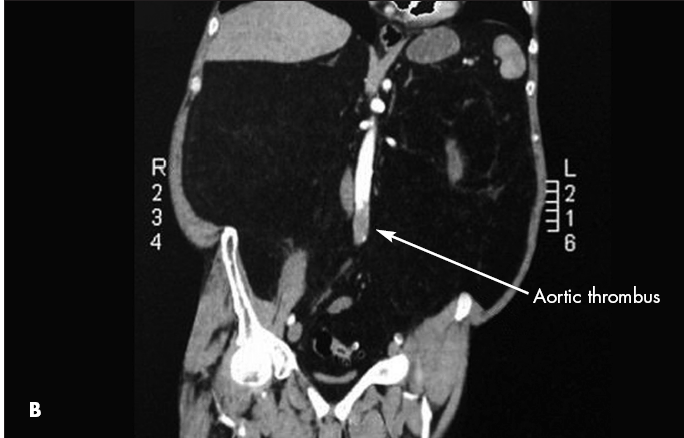

CT scans showed both a pulmonary embolus (A) and a thrombus in the wall of the abdominal aorta (B). Anticoagulation therapy was initiated. A Doppler study showed a left lower extremity deep venous thrombus. Further evaluation with transesophageal echocardiography showed a patent foramen ovale (C) and an interatrial aneurysm, with a positive bubble study.* The patient had no known history of either condition. Because of the patent foramen ovale, thrombi had traveled not only to the lungs but also to the aorta. This likely caused the spinal ischemia and paraparesis.